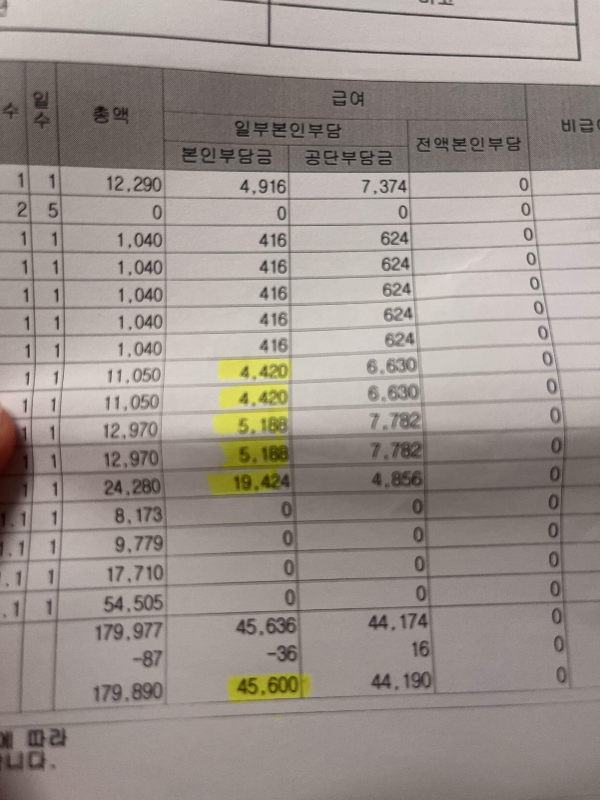

1. 진료비세부내역서

제가 산부인과 검진 항목 중 실비 환급 받았던 검진 항목은 아래와 같습니다.

1. 진료비 (약 2만 원)

2. 혈액검사비 (약 2-3만 원)

3. 질초음파 또는 복부초음파 (약 6만 원) *어떤 목적인지 중요합니다. 청구하실 때 질환에 의한 청구여야 합니다.

4. 균검사 (약 6만 원) *질염 또는 자궁경부 염증으로 인해 균검사 했을 때 해당 비용 환급받았음.

어떤 항목은 환급이 되고, 어떤 환급은 환급이 안되고 이 기준이 애매해서 환급받았던 금액에 대해 체크해 봤는데 모두 급여에 해당하는 부분이 많았습니다. 비급여에 대한 금액을 실비로 환급받는 경우는 특약이 있는 경우인듯하고, 급여 처리된 금액이라면 난임치료 또는 미용치료 목적이 아닌 이상 질환에 의한 치료인 경우 환급 가능한 것으로 보입니다.